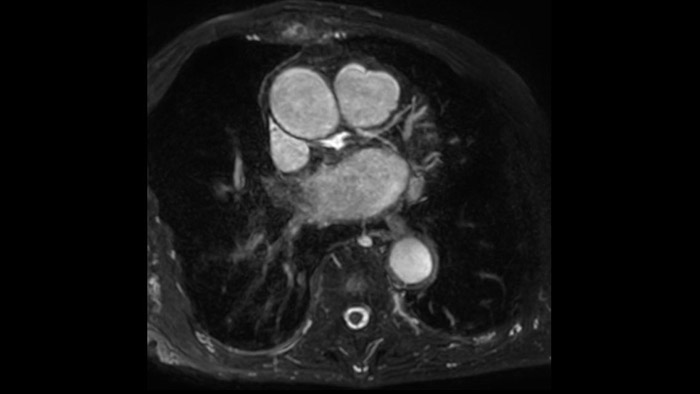

Comprehensive cardiac MR imaging

Diagnostic and prognostic utility of cardiac MR is increasing. Assess the anatomy and function of the heart using cine acquisitions, acquire information about perfusion and viability of the cardiac tissue, visualise potential edema with black blood sequence, access and even quantify tissue characterisation with CardiacQuant.